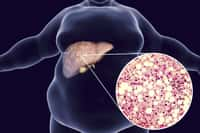

Disponible notamment sous les marques Doliprane, Efferalgan ou Dafalgan, le paracétamol est l'antidouleur le plus vendu en France. Disponible en vente libre dans les pharmacies pour un prix modeste, il est pourtant loin d'être anodin. Lorsqu'il est métabolisé, le paracétamol entraîne la formation d'un composé hautement toxique, la N-acétyl p-benzoquinone imine (NABQI). Cette substance est normalement éliminée par le glutathion, une protéine produite par le foie. Mais cette dernière est rapidement saturée lorsque l'on dépasse la dose maximale et le NABQI empoisonne alors le foie.

Surdosage au paracétamol : la première cause de greffe de foie en France